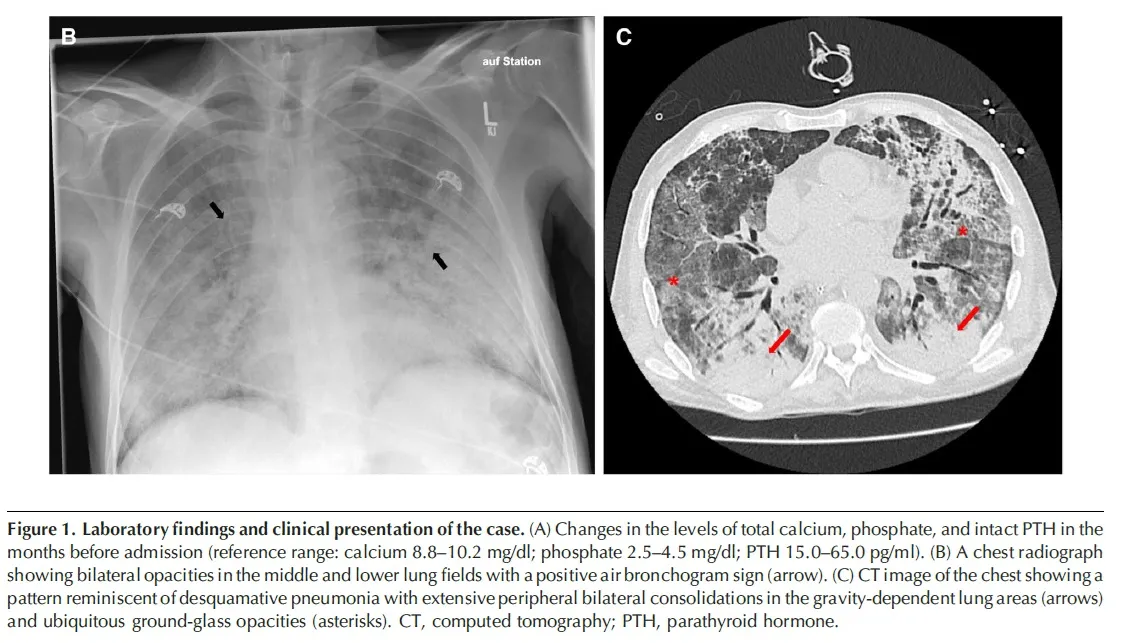

Na admissão os sinais vitais: temperatura de 37,4°C, pressão arterial de 107/42 mm Hg, frequência cardíaca de 64 batimentos por minuto, frequência respiratória de 33 respirações por minuto e saturação de oxigênio de 94% em 6 L por minuto de oxigênio. Havia crepitações inspiratórias nas bases pulmonares

* A radiografia de tórax mostrou infiltrados no pulmão esquerdo e a tomografia computadorizada revelou consolidações extensas com opacidades em vidro fosco nos lobos inferiores de ambos os pulmões.

A investigação diagnóstica subsequente revelou pneumonia por Pneumocystis jirovecii (PPJ). Apesar do